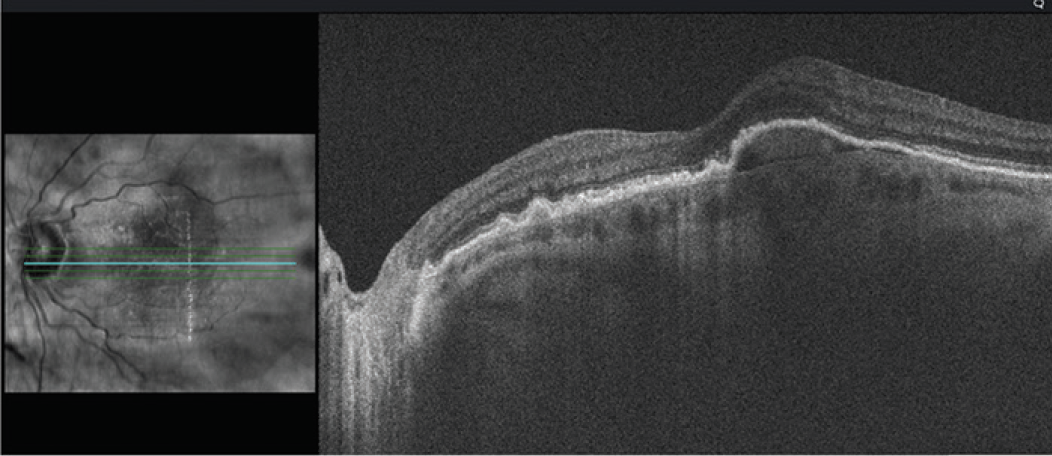

- SRF was finally resolved after nine monthly injections, and a plan was made to continue frequent monthly injections (Figure 3)

Figure 3. Full resolution of the SRF was achieved after 9 monthly injections.